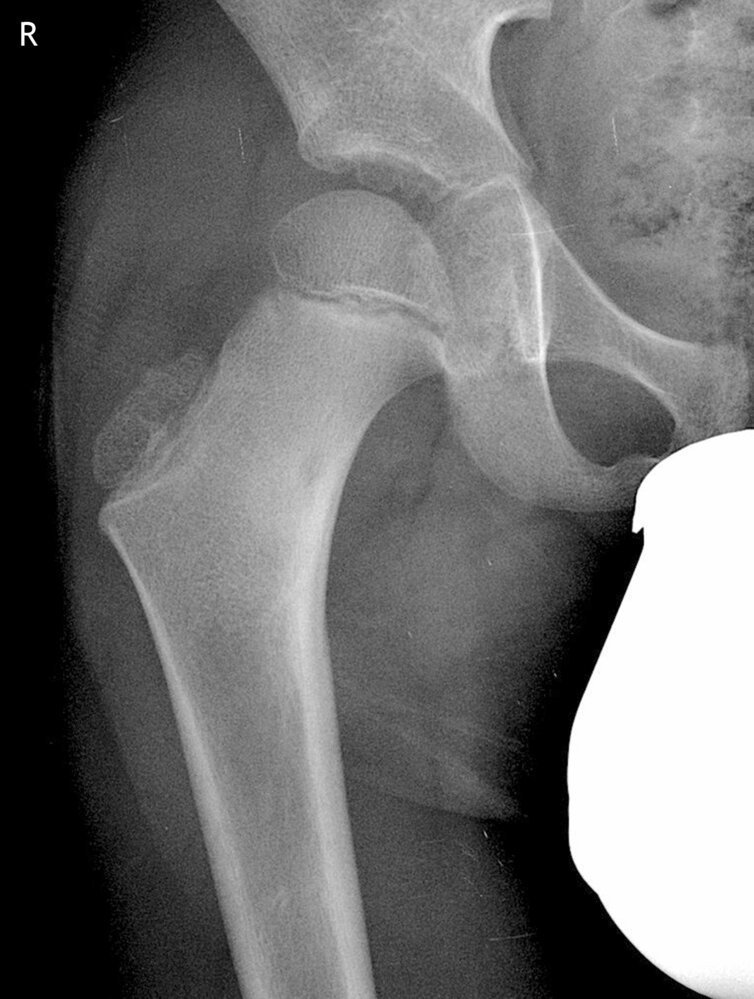

• Description: benign but locally aggressive tumor composed of giant cells that arise from the bone marrow [1]

• Epidemiology: peak incidence between 20 and 40 years

• Clinical features

• Found in the epiphysis or metaphysis of long bones (especially knee region)

• Pathological fractures

• Local pain and swelling

• Limited range of motion

• Diagnostics

• X-ray: multicystic osteolytic lesions (soap-bubble appearance)

• Histopathology

• Mononuclear, RANKL-expressing cells (neoplastic)

• Multinucleated giant cells (are reactive and resemble osteoclasts)

• Treatment: curettage and bone grafting or en-bloc resection to minimize recurrence rate

• Prognosis: risk of malignant degeneration increases with age; may spread to the lungs